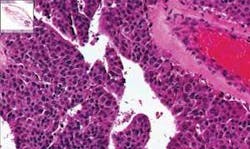

“The largest pathology image ever” produced depicts a breast tissue sample. It is available at the website of Biomedical Photometrics Inc. (BPI; Waterloo, ON Canada), where a Google Earth-like interface allows you to zoom in and out, and wander around the specimen. BPI’s website displays a number of brightfield and confocal fluorescence pathology images generated by its TISSUEscope 4000 slide scanner (www.confocal.com/RESOURCES/ImageGallery.html).